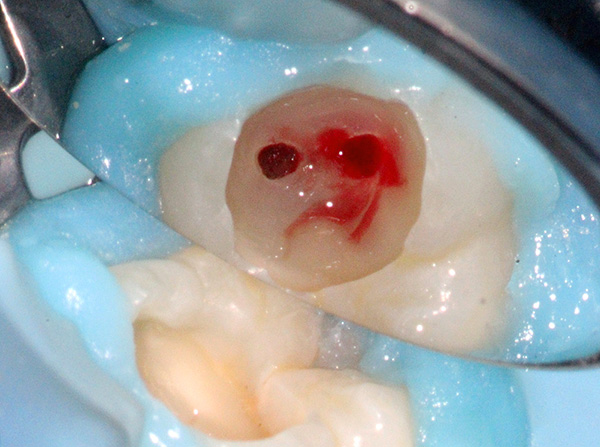

O médico não curou todos os canais do dente

Com o tratamento endodôntico, o médico precisa criar acesso a todos os canais radiculares do dente - para isso, você precisa encontrá-los todos e abrir a boca. Para pessoas diferentes nos dentes com o mesmo número de série, o número de canais pode variar e também pode haver um número diferente de ramificações.

Nota

A anatomia do sistema radicular do dente pode ser comparada a uma árvore. Nas raízes dos dentes, a polpa preenche canais especiais e, como regra, seu número corresponde ao número de raízes, mas muitas vezes existem canais adicionais.

Os canais radiculares têm uma parte estuarina (início) se comunicando com a coroa e uma parte apical (no segmento final da raiz), na qual há uma abertura anatômica - o ápice através do qual ocorre a comunicação com os tecidos circundantes das gengivas e osso da mandíbula.

Portanto, é inaceitável deixar pelo menos um canal com a infecção dentro. Deve-se entender que, nesse caso, o foco da inflamação não vai a lugar algum - ele se lembrará após o tratamento da pulpite, ou seja, o dente doerá. Pode não haver dores noturnas, mas será doloroso morder o dente por um longo tempo, e a patologia pode se transformar em uma forma crônica com a formação cistos na raiz do dente.